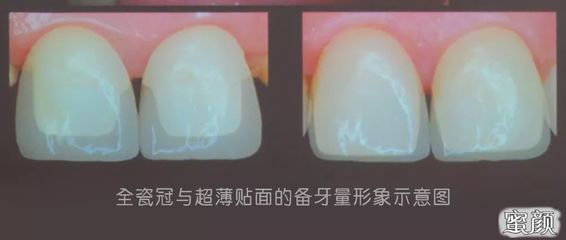

烤瓷牙是现在流行的一种牙齿,可以让你的黄牙洁白如雪。这也赢得了很多朋友的喜爱。毕竟,洁白的牙齿不是让每个人都幸运的。烤瓷牙可以有效帮助牙齿看起来更健康。那么烤瓷牙需要注意什么呢?接下来我会详细告诉你什么是烤瓷牙,烤瓷牙有什么危害,烤瓷牙有什么不适。什么是烤瓷牙?烤瓷牙是固定义齿的一种,内层是金属。

对于我们这些非专业人士来说,关于制作烤瓷牙有很多疑问。比如我应该选择什么样的烤瓷牙?为什么都是烤瓷牙,但是烤瓷牙价格差那么大?但是最大的担心应该是做了烤瓷牙之后有问题。如果烤瓷牙制作不好,后果不可小觑。如果问题很小,可以修改后再次使用,但一般需要拆下重做。所以制作烤瓷牙,首先要了解烤瓷牙的基础知识。种植牙中心的专家说,烤瓷牙制作不好会出现以下问题:1。颜色不好:烤瓷牙是一种非常稳定的东西,烤瓷牙的颜色不会随着时间而改变。无论太黄还是太白,烤瓷牙都不会逐渐变得接近自己的牙齿颜色。